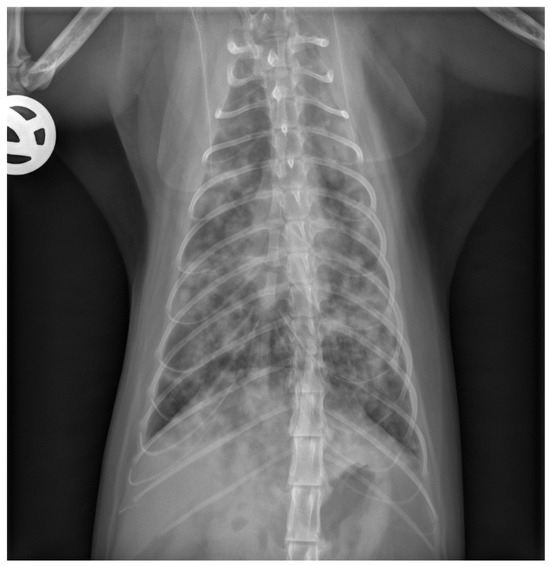

The cat was hospitalized in the intensive care unit and received supplemental oxygen (oxygen cage, 40% O2), intravenous crystalloid fluid support (Ringer’s Acetate solution), bronchodilation with theophylline (Euphylong® Injectable solution, Altana Pharma, Konstanz, Germany), amoxicillin/clavulanate (AmoxiClav®, Hikma, Munich, Germany) antimicrobial treatment, and empirical deworming with fenbendazole (Panacur®, MSD-Intervet, Unterschleißheim, Germany), and was closely monitored for any changes in its respiratory rate and effort or other complications. Carefully weighing the benefits of the current treatment strategy against the risks of AIHA relapse and the working diagnosis of secondary infectious pneumonia, cyclosporine treatment was decided to be continued. Given the severe neutropenia and lack of significant clinical improvement within 24 h, clindamycin (Cleorobe®, Zoetis, Berlin, Germany) was added to the treatment plan. The cat remained stable but tachypneic for three days, followed by an acute onset of dyspnea on day four of hospitalization. Repeat thoracic radiographs (only one image plane due to the clinical instability of the cat) revealed mildly progressive changes (Figure 2). The cat acutely decompensated, and humane euthanasia was elected by the owner.

Figure 2. Repeat thoracic radiograph after 3 days of hospitalization. This ventrodorsal view shows a progressive bronchointerstitial to alveolar lung pattern compared to the initial radiographs obtained at the time of presentation.

Diagnostic imaging revealed a normal appearance of abdominal organs (i.e., liver, spleen, kidneys, adrenal glands, pancreas, liver, gall bladder, stomach, and intestines) but marked alterations of the intrathoracic respiratory system (i.e., all lung fields). Specifically, thoracic radiographs at the time of presentation showed a mild generalized alveolar lung pattern with air-bronchograms superimposed on the cardiac silhouette and a mildly increased vertebral heart size, suggesting either pulmonary edema (cardiogenic vs. non-cardiogenic) or pneumonia (bacterial, parasitic, or other etiologies), but less likely diffuse infiltrative neoplasia (e.g., lymphoma, mast cell tumor). The NT-proBNP test was normal, supporting the suggestion that a non-cardiogenic etiology was more likely.